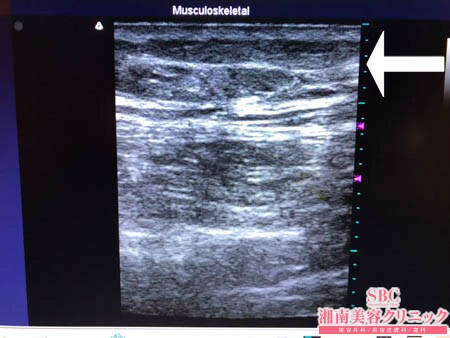

No.204149【脂肪吸引】【動画あり】湘南美容外科全ドクターの脂肪吸引最高責任者である竹田先生による脂肪吸引のフォトギャラリー!中国在住の中国人の患者様の太ももの脂肪吸引を安心で信頼できる日本で受けたい!術中3Dタッチビュー・左太もも後面